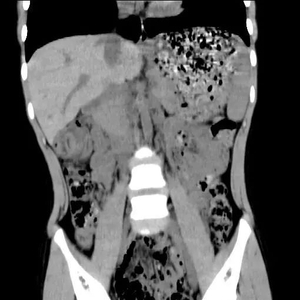

腹部CT出来后,提示结肠肝区似同心圆样改变,难道是肠套叠吗?

我立即嘱患儿完善腹部B超,结果也提示肠套叠!那这万万不可马虎,又立即予空气灌肠,但空气灌肠后未见明显肠套叠,升结肠却发现了类圆形块影……这是怎么回事?